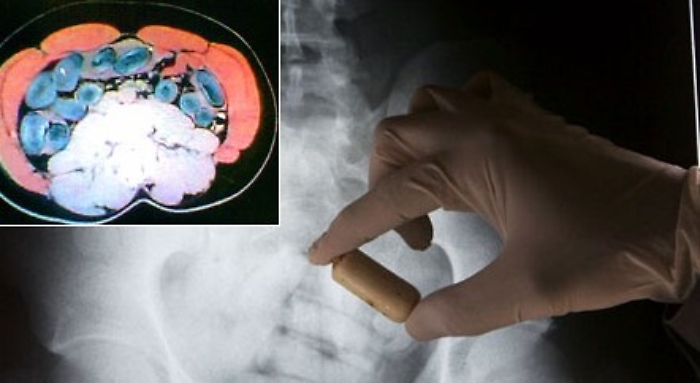

Corriere della droga ghanese fermato a Favara con 10 ovuli nella pancia

Favara (Agrigento) - In viaggio dalla Spagna all’Italia con 165 gr di eroina purissima nello stomaco. Un corriere della droga, 45 anni, ghanese, residente nella penisola iberica, è stato fermato a Favara (Agrigento) dai carabinieri mentre chiedeva un passaggio a una ignara giovane coppia. Portato all’ospedale San Giovanni di Dio di Agrigento, le radiografie hanno rilevato che nello stomaco dell’uomo c'erano 10 ovuli con eroina.